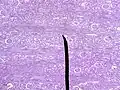

- Микрофотография коркового слоя паренхимы почки

Поверхность среза почечной паренхимы благодаря расположенным в области колонн извитым в различных направлениях канальцам (лат. tubuli contorti) отличается от остальной ткани пирамид, имеющей характерную радиарную исчерченность. Участки ткани с подобной макроскопически видимой радиарной (лучевой) штрихованностью, наблюдаются в корковом слое (лат. pars radiata). При микроскопическом исследовании можно убедиться, что они связаны с веществом пирамиды и являются выростами коркового слоя, проникающими через мозговой слой, достигая его периферии. В пределах одной и той же пирамиды несколько подобных образований ограничивают поля кортикального слоя, лишённые радиарной (лучевой) штрихованности — (лат. pars convoluta), выделяя в нём обособленные дольки (лат. lobuli corticales).